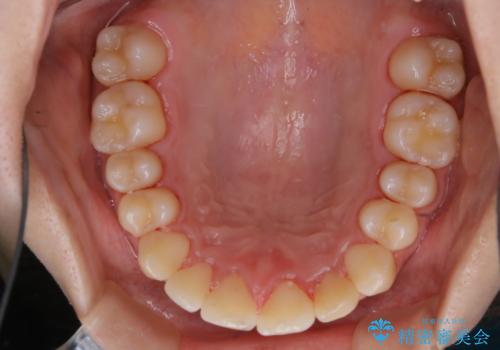

矯正治療終了後にPMTC(Professional Mechanical Tooth Cleaning)

- 矯正治療が終了したため、クリーニングでもきれいにしたいとのことでした。PMTC60分コースを行いました。

矯正治療やセラミックなどによる被せ物の治療終了のタイミングではクリーニングを行い、汚れや着色の除去、歯と歯の間・歯と歯肉との境目などのケアをしっかりすることをおすすめしています。

ご自身での歯ブラシ・セルフケアを行うと同時に、定期的なクリーニング(PMTC)を行うことで、いつまでも健康な歯を保つことができます。